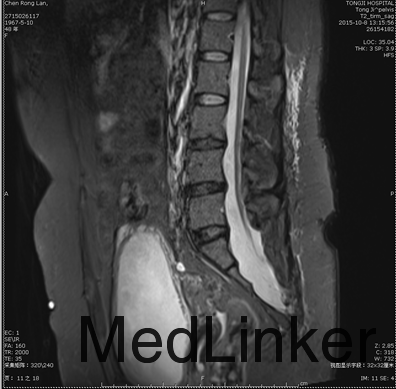

查体:体温36.4℃脉搏80次/分(规则)呼吸19次/分(规则),血压138/80mmHg,双肾区无叩击痛,双下肢无水肿,外生殖器无见明显异常。 辅助检查:2015-10-03尿常规:红细胞(隐血)1+ 白细胞(粒)1+尿蛋白2+白细胞计数45.0/ul; 2015-09-30彩超示:左肾体积缩小,尿潴留。发病以来精神尚可,小便如上述,大便干燥,体重无明显改变。 尿动力学检查示:膀胱收缩乏力(神经源性);膀胱感觉迟钝,残余尿增多;建议行间歇导尿治疗。 骶丛神经MRI平扫及功能成像:1、盲囊囊性扩张, 骶尾骨发育不良;2、脊髓圆锥下移(S1下缘水平),脊髓栓系可;3、右侧S3、4神经根显示欠清,右侧S2、左侧S2、3、4神经根显示纤细;4、宫颈纳氏腺囊肿;5、膀胱异常改变,考虑为神经源性膀胱;6、L4/5、L5/S1椎间盘膨出,双侧L4、5神经根受推移。